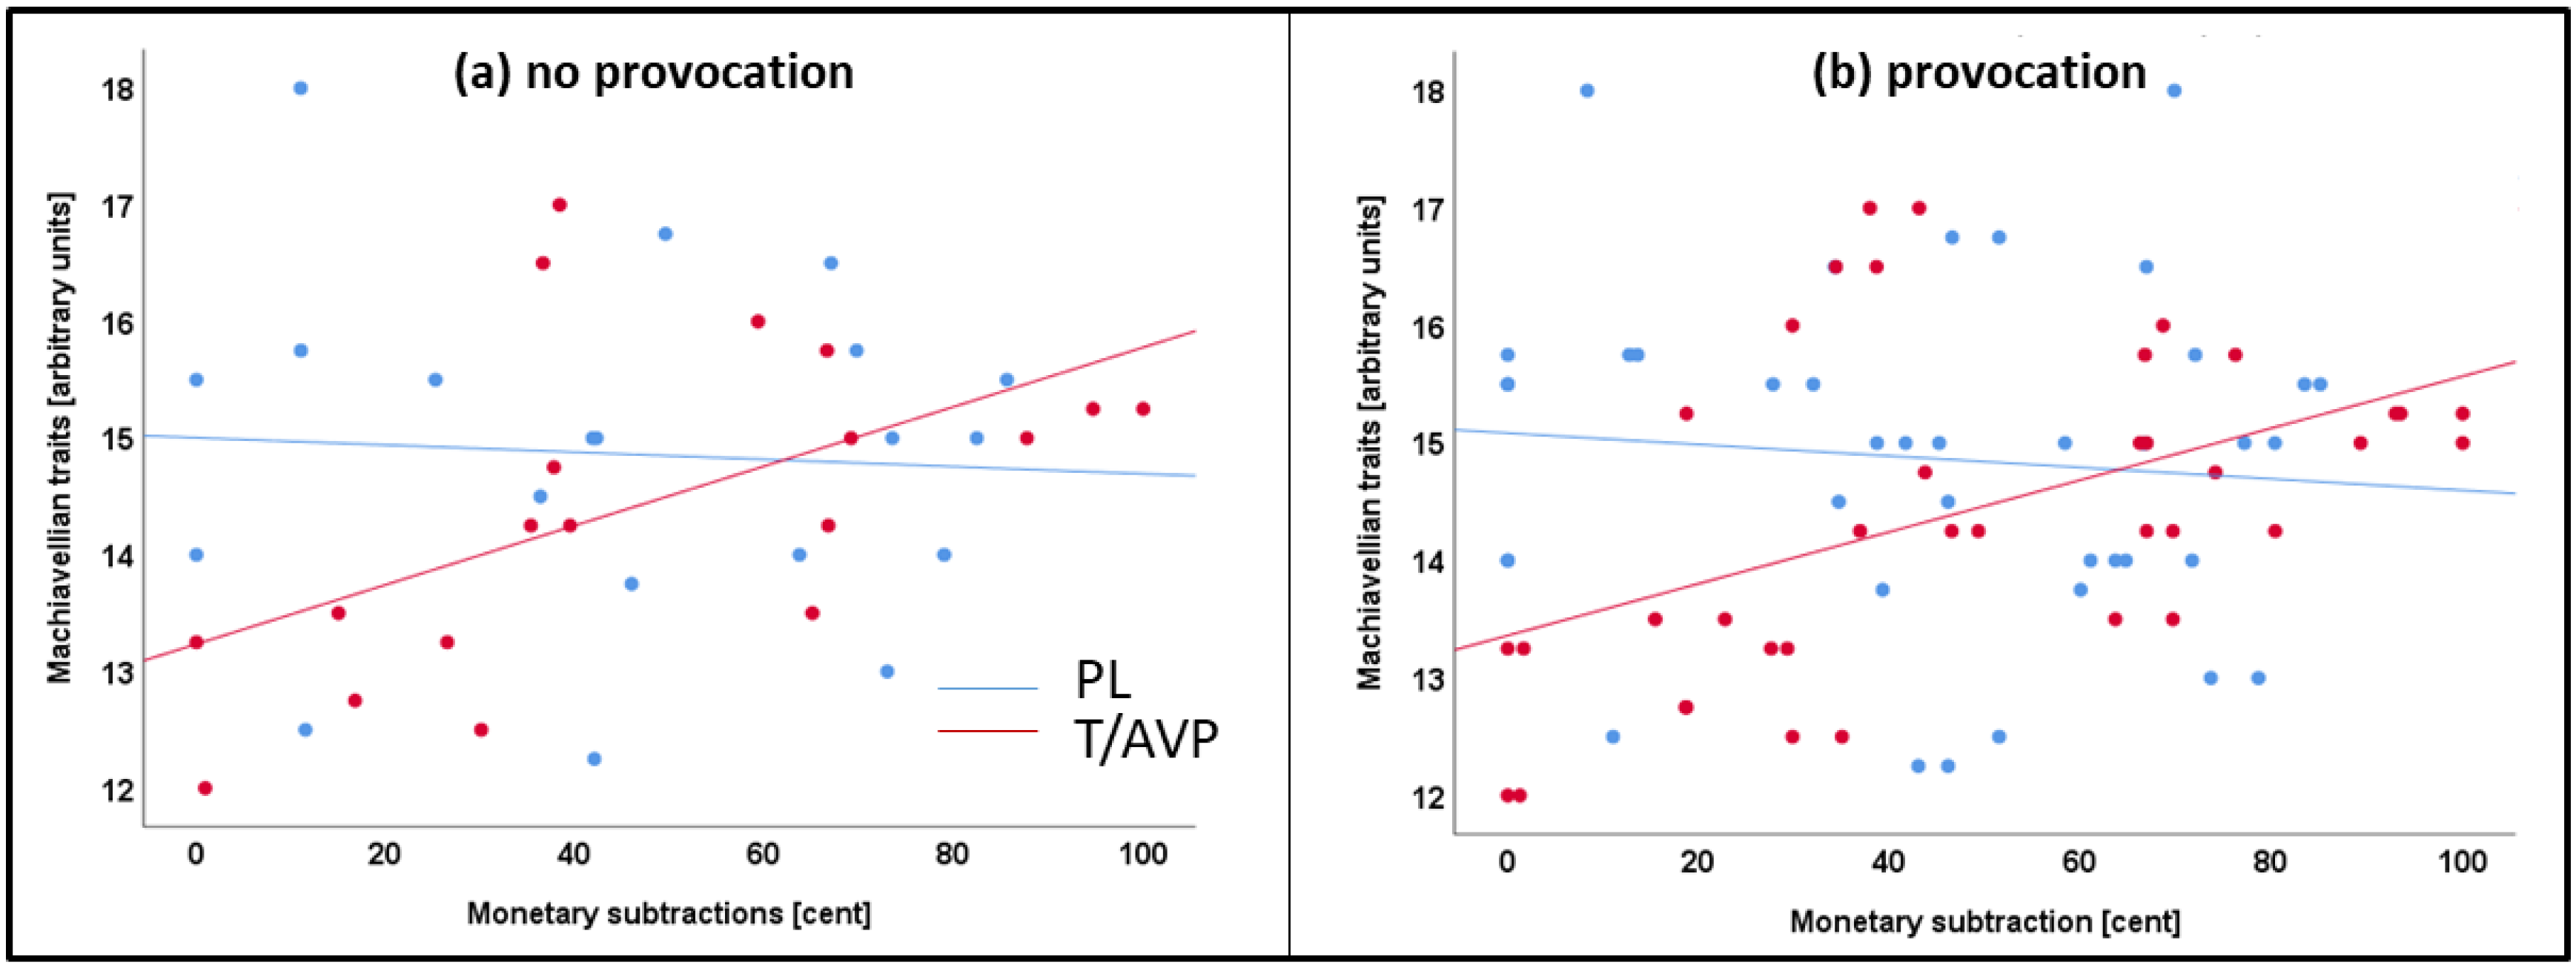

3.3. Task Behavior

4.3. Machiavellian Traits